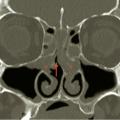

Polypose nasosinusienne

La polypose nasosinusienne est une rhinosinusite diffuse caractérisée par la présence de polypes bilatéraux dans les cavités nasales venant du massif ethmoïdal. Sa physiopathologie repose sur une inflammation chronique de la muqueuse des cavités nasales et sinusiennes marquée par une infiltration éosinophilique plus ou moins…